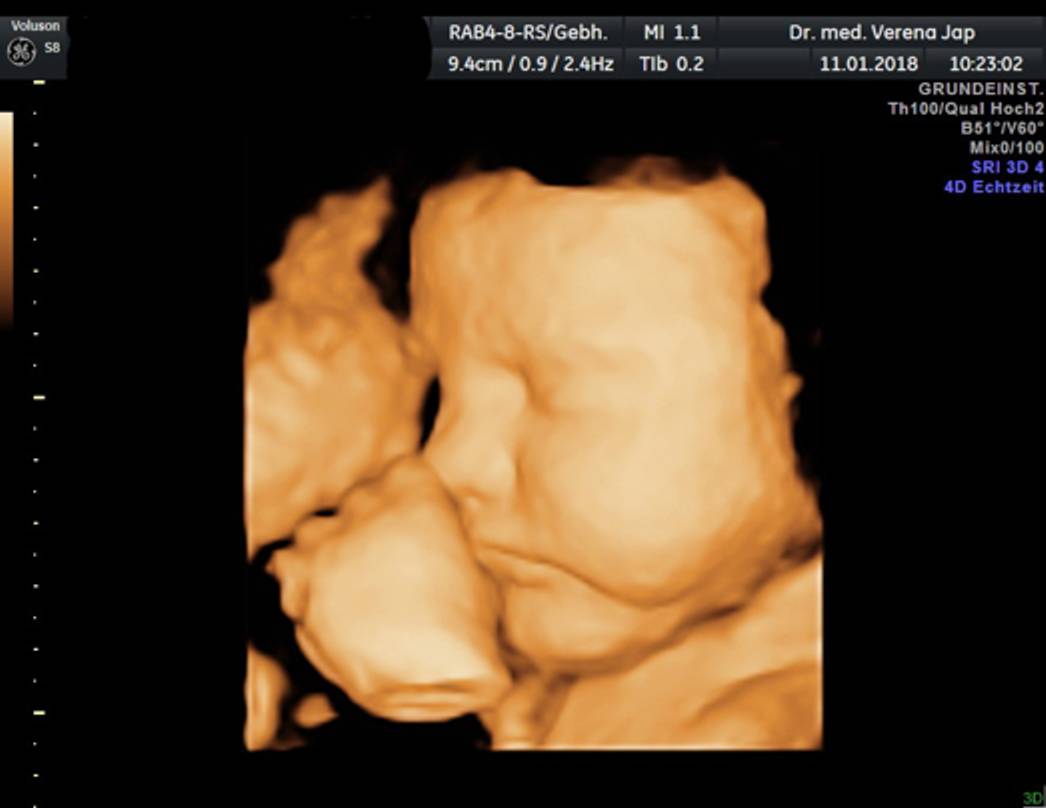

Die 3D-Ultraschalltechnik ermöglicht eine räumliche Darstellung des ungeborenen Kindes

Sie bietet den werdenden Eltern die Möglichkeit, unglaublich realistische Bilder ihres Babys zu bekommen. 3D-Ultraschall funktioniert ähnlich wie herkömmlicher Ultraschall, es werden jedoch viele verschiedene Schnittbilder zu einem dreidimensionalen Bild umgerechnet. Für das Ungeborene ist diese Technik daher vollkommen harmlos. Allerdings sind wir auf die Mitarbeit Ihres Kindes angewiesen, denn schöne Aufnahmen gelingen nur bei einer guten Kindslage. Das beste Zeitfenster liegt ca. zwischen der 25. und 30. Schwangerschaftswoche. Die 3D/4D Ultraschalluntersuchung kann natürlich auch von Schwangeren in Anspruch genommen werden, die nicht in unserer Praxis behandelt werden.